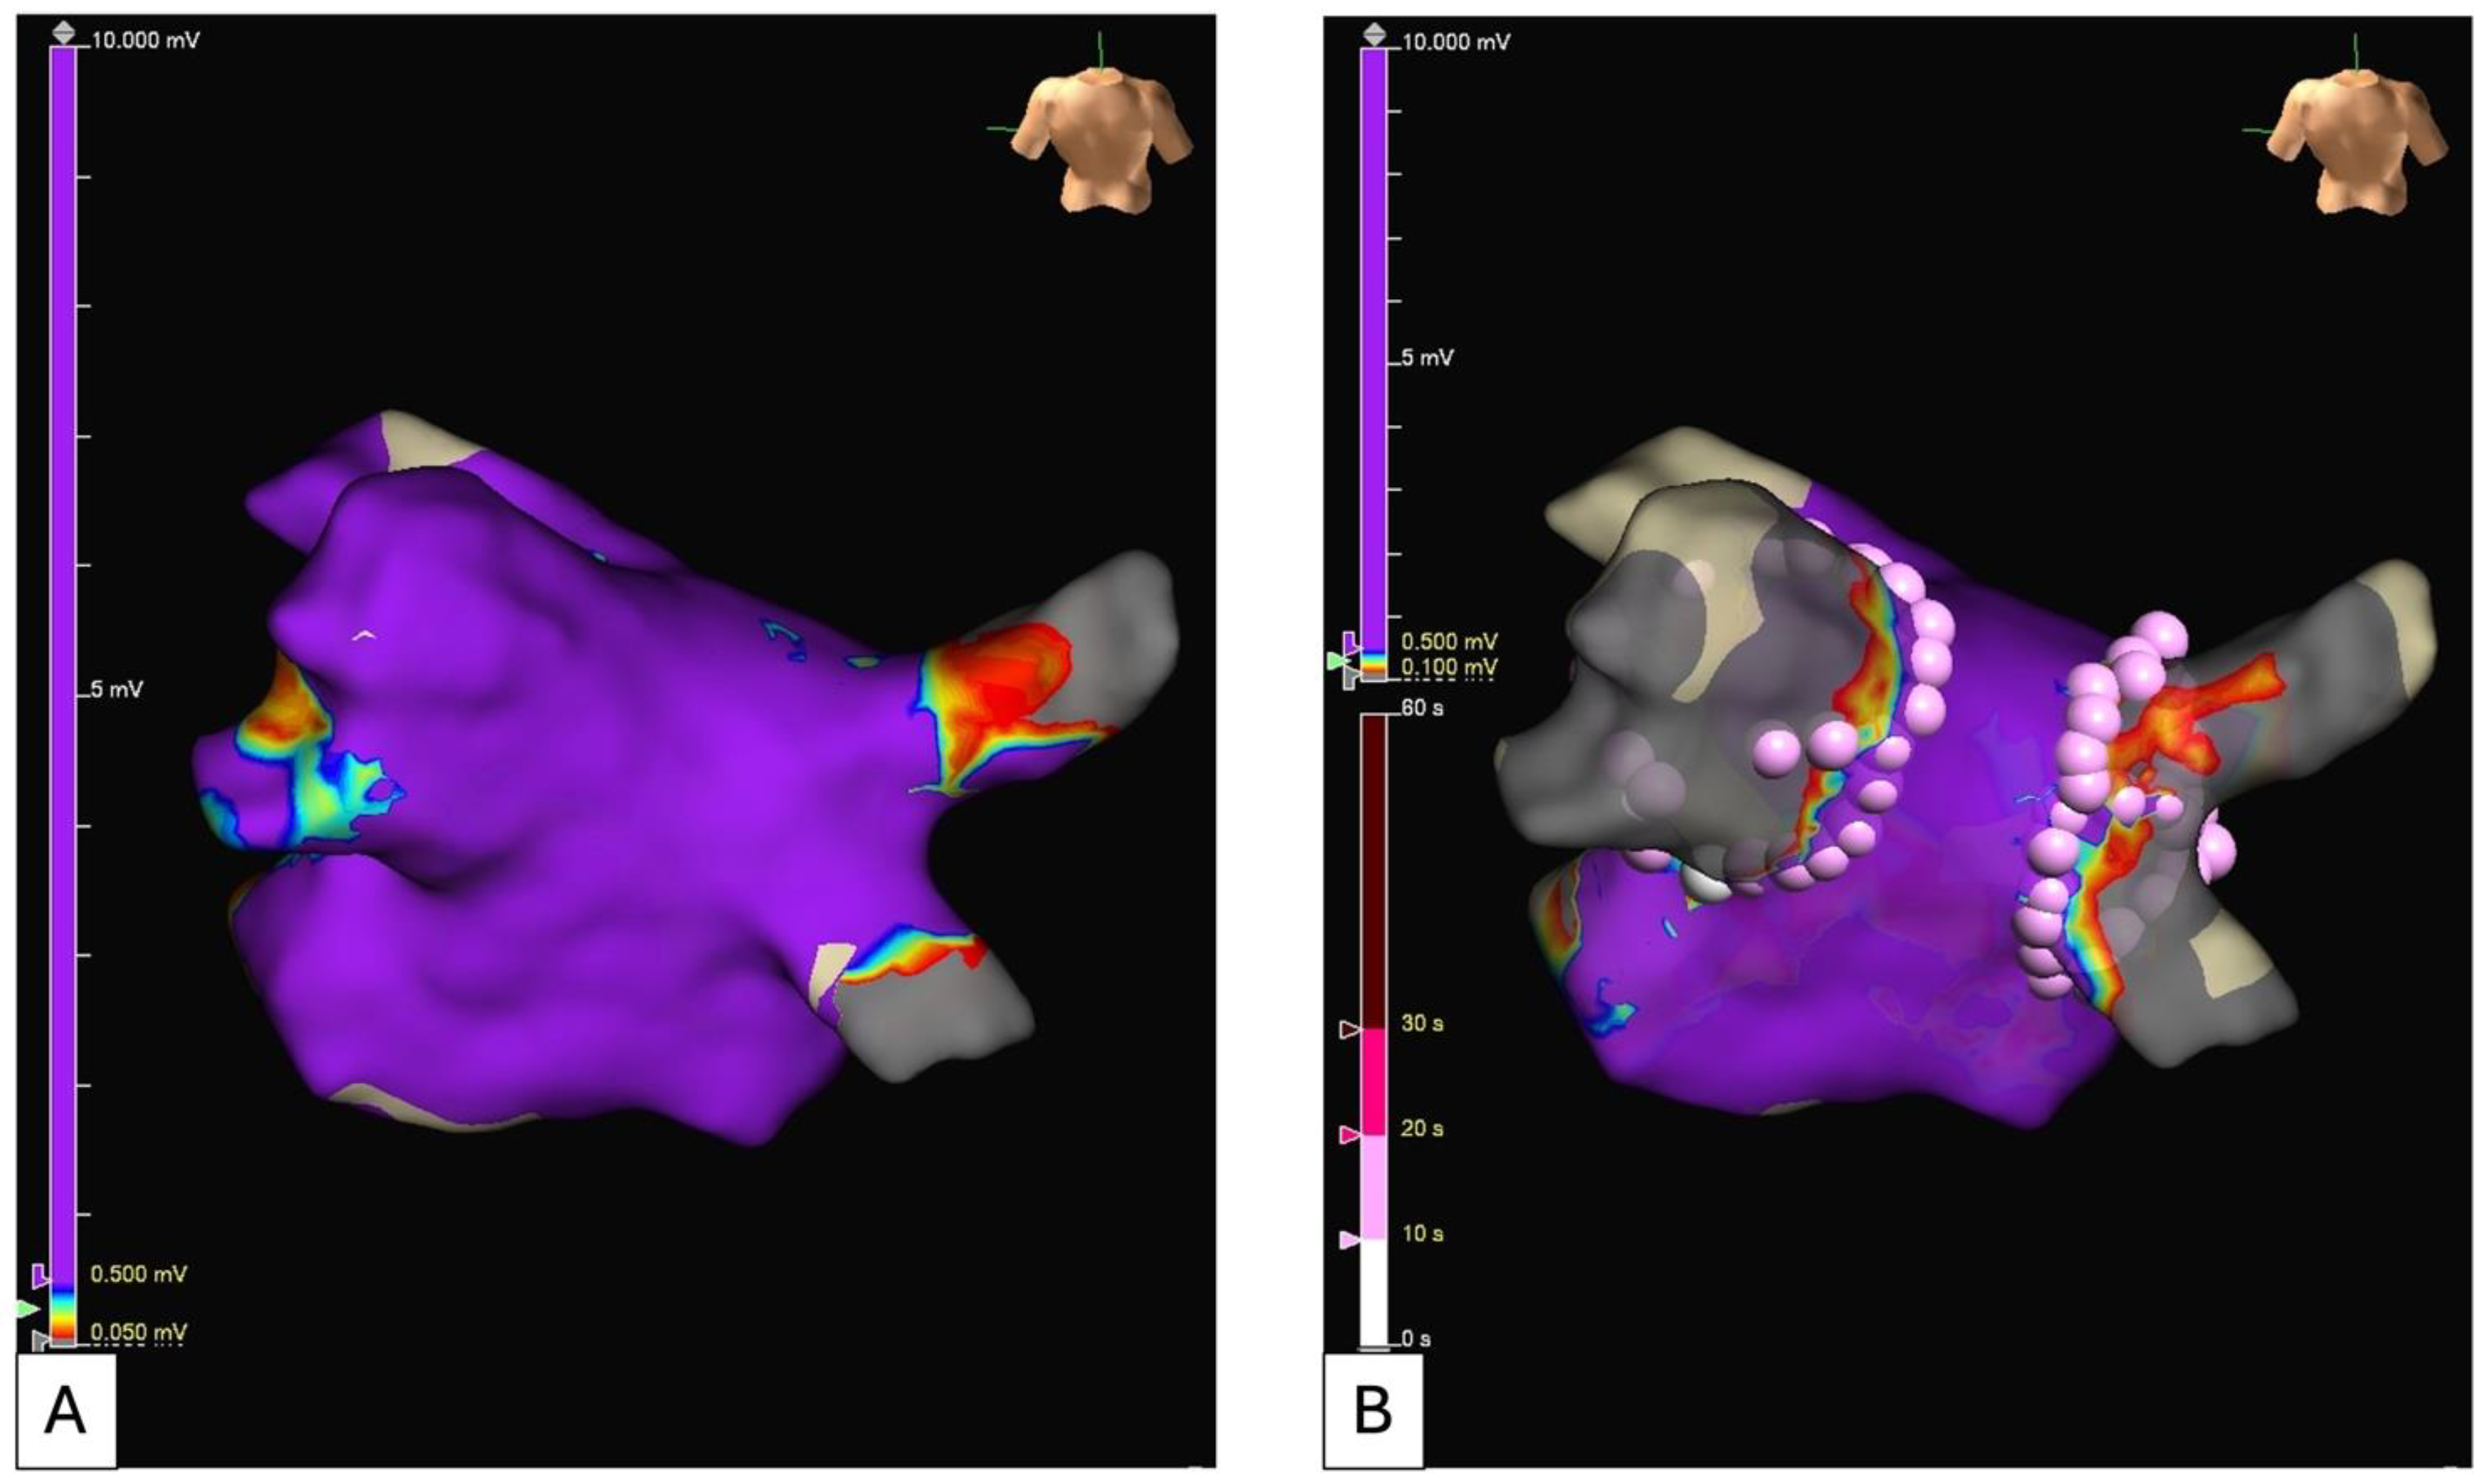

- Rolf, S.; Kircher, S.; Arya, A.; Eitel, C.; Sommer, P.; Richter, S.; Gaspar, T.; Bollmann, A.; Altmann, D.; Piedra, C.; et al. Tailored Atrial Substrate Modification Based on Low-Voltage Areas in Catheter Ablation of Atrial Fibrillation. Circ. Arrhythmia Electrophysiol. 2014, 7, 825–833. [Google Scholar] [CrossRef] [PubMed]

- Madaffari, A.; Knecht, S.; Spies, F.; Schaer, B.; Kühne, M.; Sticherling, C.; Osswald, S. Epicardial Connection: The Achilles Heel of Gap Mapping After Wide Antral Pulmonary Veins Isolation. JACC Clin. Electrophysiol. 2019, 5, 1356–1357. [Google Scholar] [CrossRef] [PubMed]